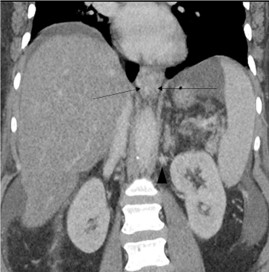

CT angiogram of the chest was negative for a pulmonary embolism or pneumonia. Abdominal CT demonstrated a cirrhotic appearing liver with mild ascites, paraesophageal varices, and recanalization of the umbilical vein consistent with collateral venous flow in the setting of portal hypertension (Figure 1).

Figure 1: Contrast Enhanced CT chest, abdomen and pelvis on admission: Coronal image showing cirrhotic liver, ascites and paraesophageal collaterals (arrow). Also visualized are spleno-renal collaterals (arrow head).